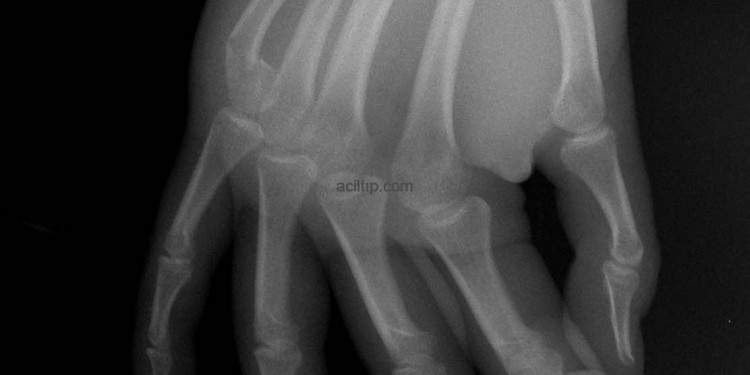

Ekstremite Kırıkları-6

Boksör kırığı